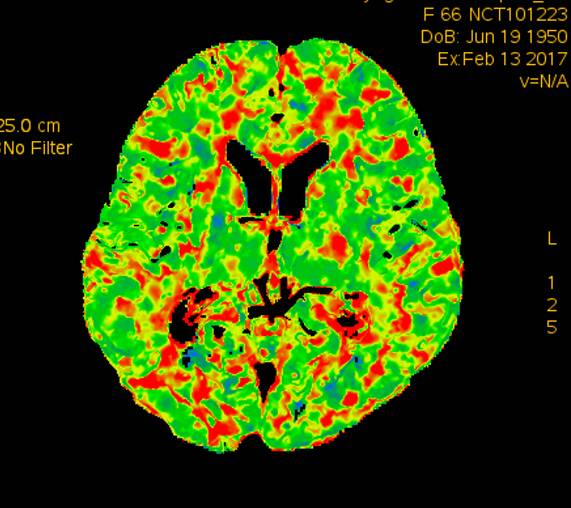

术前CTP示:右侧大脑半球灌注较差。

术后2个月患者未再诉右眼黑曚。复查CTP示:颅内灌注明显改善。

术前灌注成像,右侧大脑半球灌注较差。

此次分享两例颈动脉闭塞复合手术开通病例。第一例为颈内动脉长段闭塞,从颈内动脉起始段开始闭塞。患者术前存在眼动脉缺血事件及右侧半球灌注不足。颈内动脉剥脱后,颈内动脉可淡淡显影,为微导管通过创造条件。微导管通过后,顺利完成球囊扩张及支架植入,完全开通右侧颈内动脉。第二例为右侧颈总动脉闭塞患者,虽有颈外动脉代偿,但仍存在TIA及右侧大脑半球灌注不足。经颈动脉内膜剥脱后,造影可见颈总动脉显影,但管腔严重不规则,经球囊扩张及支架植入后,颈总动脉显影好。两例患者术后7天复查颈动脉CTA,均显示颈内动脉起始处较术后造影增粗。